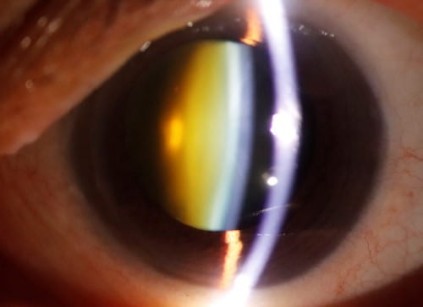

Πυρηνικός σκληρυντικός καταρράκτης

Ο καταρράκτης είναι η κύρια αιτία αναστρέψιμης μείωσης της όρασης στην Ελλάδα και σε όλο το δυτικό κόσμο. Πρόκειται για την θόλωση του κρυσταλλοειδούς φακού του ματιού. Ο φυσιολογικός φακός του ανθρώπου με την πάροδο των ετών και συνηθέστερα μετά την ηλικία των 50 θολώνει καθώς γερνάει με αποτέλεσμα να εμποδίζει το φως να εισέρχεται στο μάτι. Αντί δηλαδή να διαπερνούν οι ακτίνες φωτός τον φακό και να εστιάζονται στον αμφιβληστροειδή και ειδικότερα στην ωχρά κηλίδα προσφέροντας καλή οπτική οξύτητα, αυτές διαχέονται και δεν εστιάζονται σε ένα σημείο προκαλώντας θόλωση της όρασης. Υπάρχουν διάφορα είδη καταρράκτη, άλλα που προκαλούν σταδιακή έκπτωση της όρασης και άλλα πιο ραγδαία. Όλες οι μορφές ωστόσο οδηγούν στο ίδιο αποτέλεσμα αν δεν αντιμετωπιστούν χειρουργικά, την σημαντική πτώση της όρασης.

Όπως προαναφέρθηκε η αντιμετώπιση του καταρράκτη καθώς ωριμάζει είναι χειρουργική. Η σύγχρονη χειρουργική μέθοδος που χρησιμοποιείται παγκοσμίως ονομάζεται φακοθρυψία. Προήλθε από τον Charles Kelmann, ο οποίος παρατήρησε τα οφέλη του υπερήχου σε ορισμένες κλινικές πράξεις των οδοντιάτρων και επιχείρησε να την χρησιμοποιήσει τροποποιημένη στους οφθαλμούς. Η μέθοδος της φακοθρυψίας  περιλαμβάνει την αφαίρεση του καταρρακτικού φακού του ματιού, ο οποίος  θρυμματίζεται και αναρροφάται με την χρήση υπερήχων και εν συνεχεία την τοποθέτηση κατάλληλου τεχνητού ενδοφακού. Η φακοθρυψία μείωσε σημαντικά τις επιπλοκές σε σχέση με παλαιότερα, ελαττώνοντας παράλληλα τον χρόνο παραμονής στην κλινική και προσφέροντας υψηλά ποσοστά επιτυχίας.